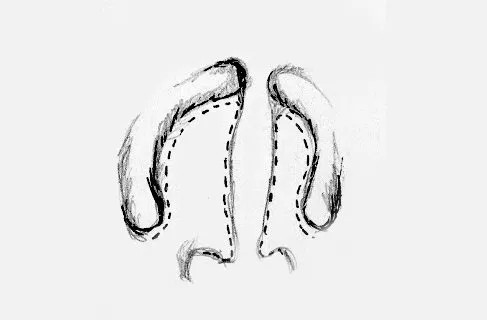

Motlle nasoalveolar o NAM (Grayson)

Consisteix en una placa obturadora del paladar amb una prolongació per donar forma a l'ala nasal. La placa es va canviant cada poc temps per tal d'anar reduint la fissura.